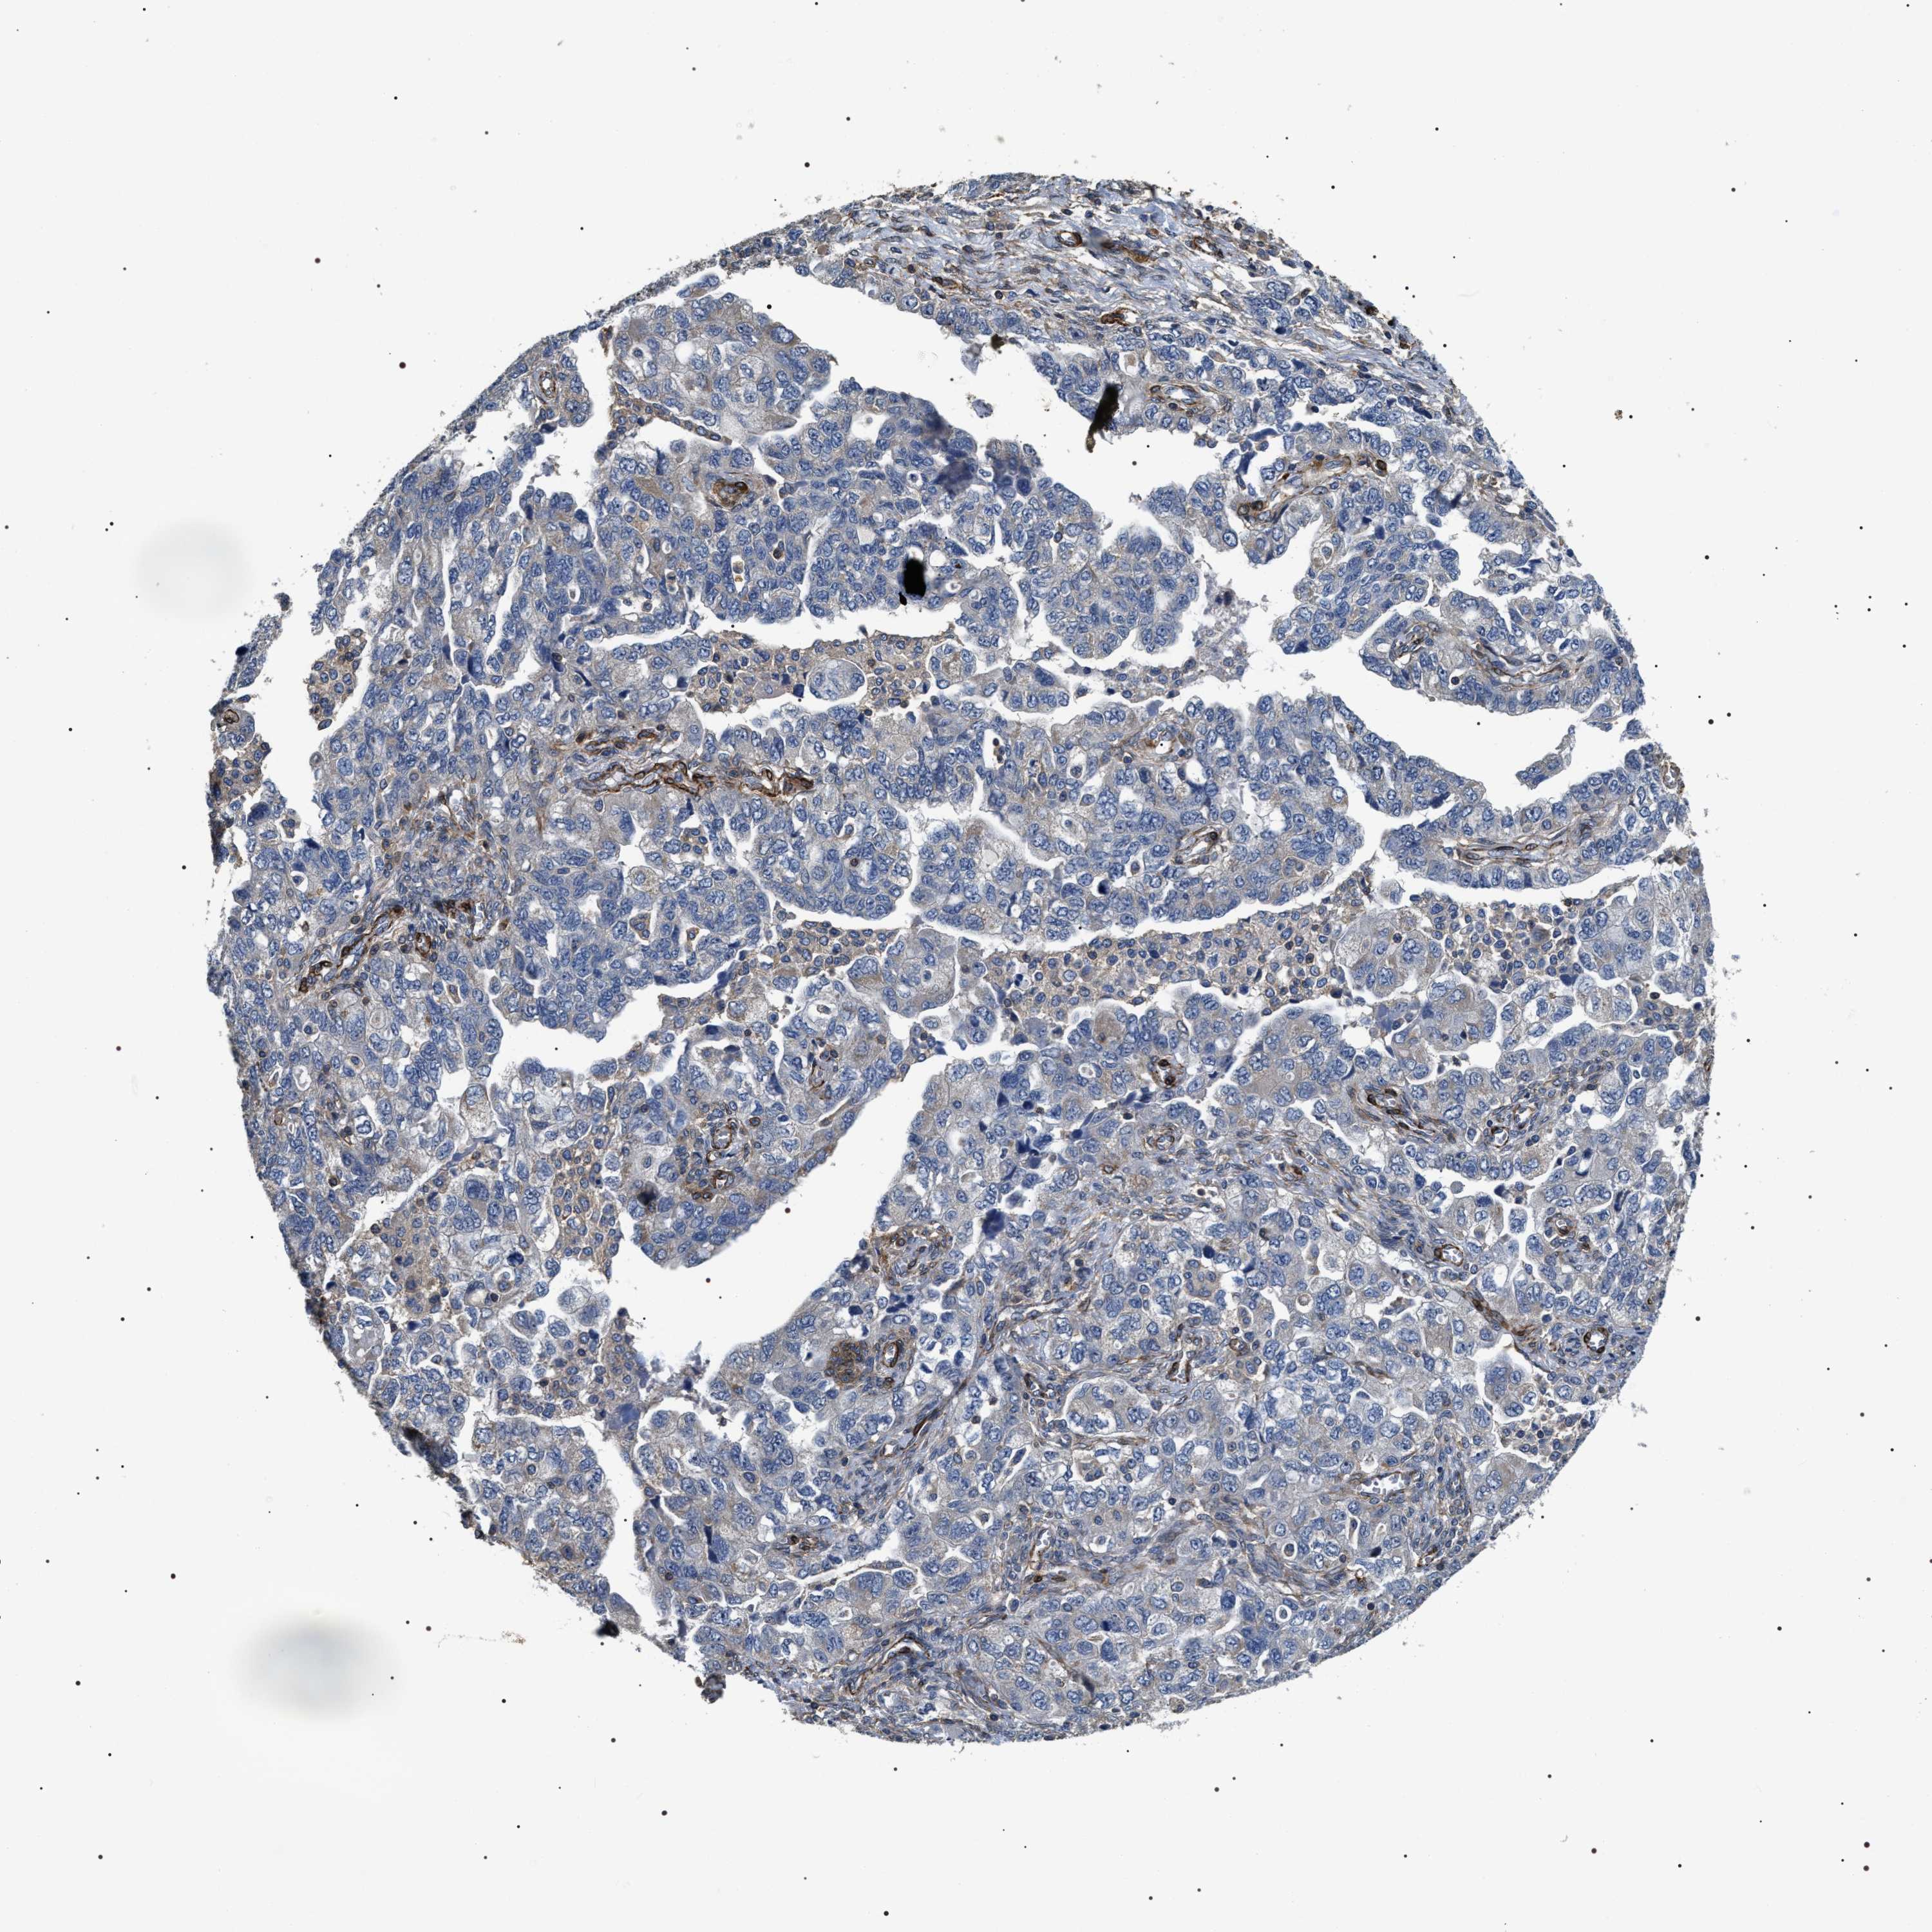

OVARIAN CANCER - Protein expressioni

A mouse-over function shows sample information and annotation data. Click on an image to view it in a full screen mode. Samples can be filtered based on level of antibody staining by selecting one or several of the following categories: high, medium, low and not detected. The assay and annotation is described here.

Note that samples used for immunohistochemistry by the Human Protein Atlas do not correspond to samples in the TCGA dataset.

Antibody stainingi

Antibody staining in the annotated cell types in the current human tissue is reported as not detected, low, medium, or high, based on conventional immunohistochemistry profiling in selected tissues. This score is based on the combination of the staining intensity and fraction of stained cells.

Each image is clickable and will lead to virtual microscopy that enables deeper exploration of all samples and also displays staining intensity scores, fraction scores and subcellular localization as well as patient and tissue information for each sample.

Antibody HPA020386

Staining

High

Medium

Low

Not detected

Intensity

Strong

Moderate

Weak

Negative

Quantity

>75%

75%-25%

<25%

None

Location

Nuclear

Cytoplasmic/membranous

Cytoplasmic/membranous,nuclear

Cystadenocarcinoma, serous, NOS

Carcinoma, endometroid

Cystadenocarcinoma, mucinous, NOS

Carcinoma, NOS